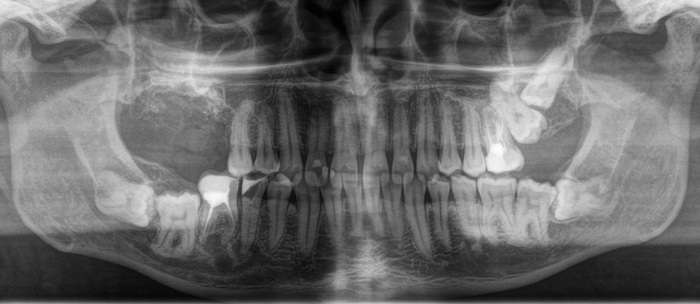

После изучения снимка и дополнительной консультации с терапевтом были приговорены практически все жевательные зубы, кроме левой нижней шестерки. (На снимке справа)

После того, как я предупредил о ВСЕХ возможных рисках и последствиях, плюс о шансе, что условий для имплантации на верхней челюсти в дальнейшем может и не представиться, пациент согласился. Я начал с удаления зубов на верхней челюсти справа. (на снимке слева)

Как вы думаете, сколько ушло у меня на удаление этих трех зубов?

Три зуба – 70 минут (от анестезии до последнего шва).

В лунки были уложены гемостатические губки, рана наглухо ушита.

Примерно через месяц мы приступили к удалению трех зубов на нижней челюсти, что заняло чуть меньше часа – около 50 минут.